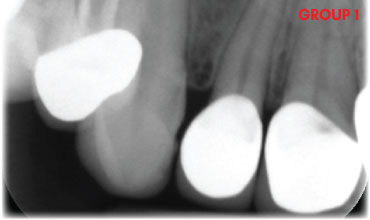

- How to accurately diagnose and evaluate radiographs.